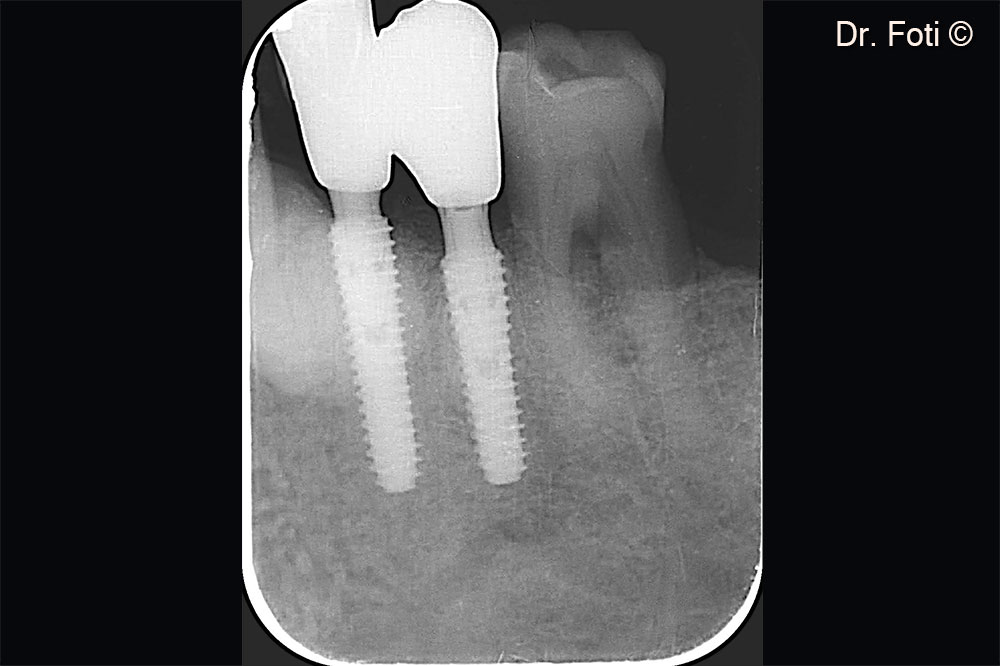

Suture without tension on the edges. Post-operative x-ray.

The follow-up radiograph shows newly formed bone between the canine and implant in position 34